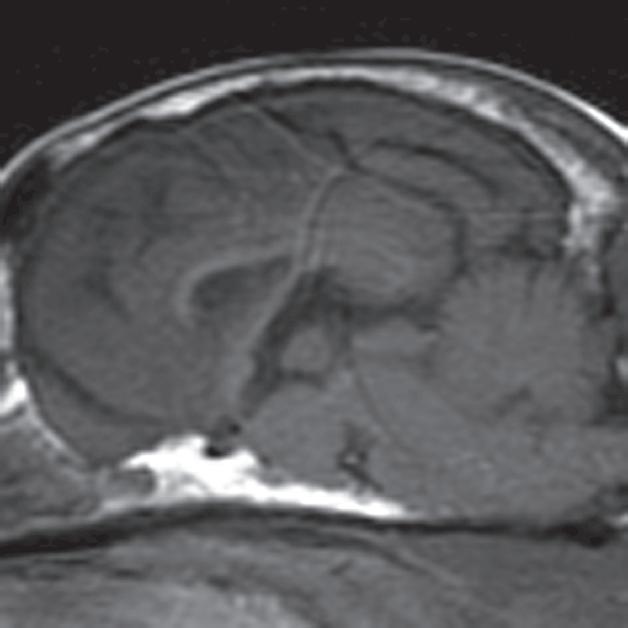

Rycina 2.9.12. Gruczolak przysadki (pies) MR

Badanie wykonano u 14-letniej, kastrowanej samicy szpica z przechyleniem głowy i występującym od niedawna chodzeniem w kółko w prawą stronę. Ryciny a–c to reprezentatywne obrazy w płaszczyźnie poprzecznej na poziomie dołu przysadki. Ryciny d–f to analogiczne obrazy w płaszczyźnie strzałkowej. Przysadka mózgowa była znacznie powiększona (wysokość = 10 mm, szerokość = 10 mm), izointensywna w obrazach T1-zależnych (a, d) i łagodnie hiperintensywna w obrazach T2-zależnych (b, e) w porównaniu z istotą szarą głęboką. Stwierdzono również poszerzenie układu komorowego (wentrikulomegalię), które może wynikać z częściowej niedrożności. Przysadka uległa jednorodnemu wzmocnieniu kontrastowemu (c, f), a w badaniu pośmiertnym wykazano, że miała postać dobrze odgraniczonej, kulistej masy (g). Potwierdzono, że zmiana była makrogruczolakiem przysadki